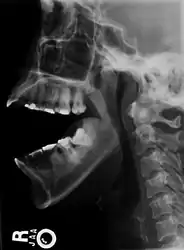

Side view of the skull with anterior dislocation of jaw. -